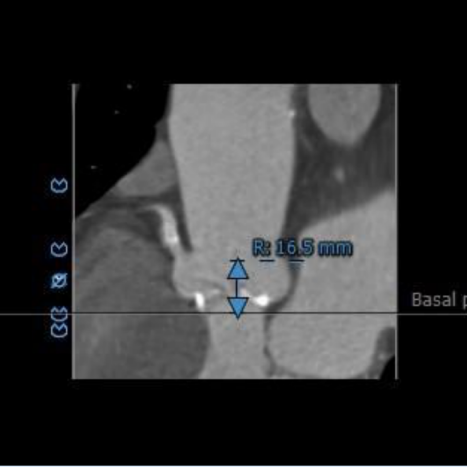

左冠开口高度15.3mm,右冠开口高度16.5mm,高度可,根据瓦氏窦内径和瓣叶长度综合判断,冠脉堵塞风险小。

冠脉高度测量: